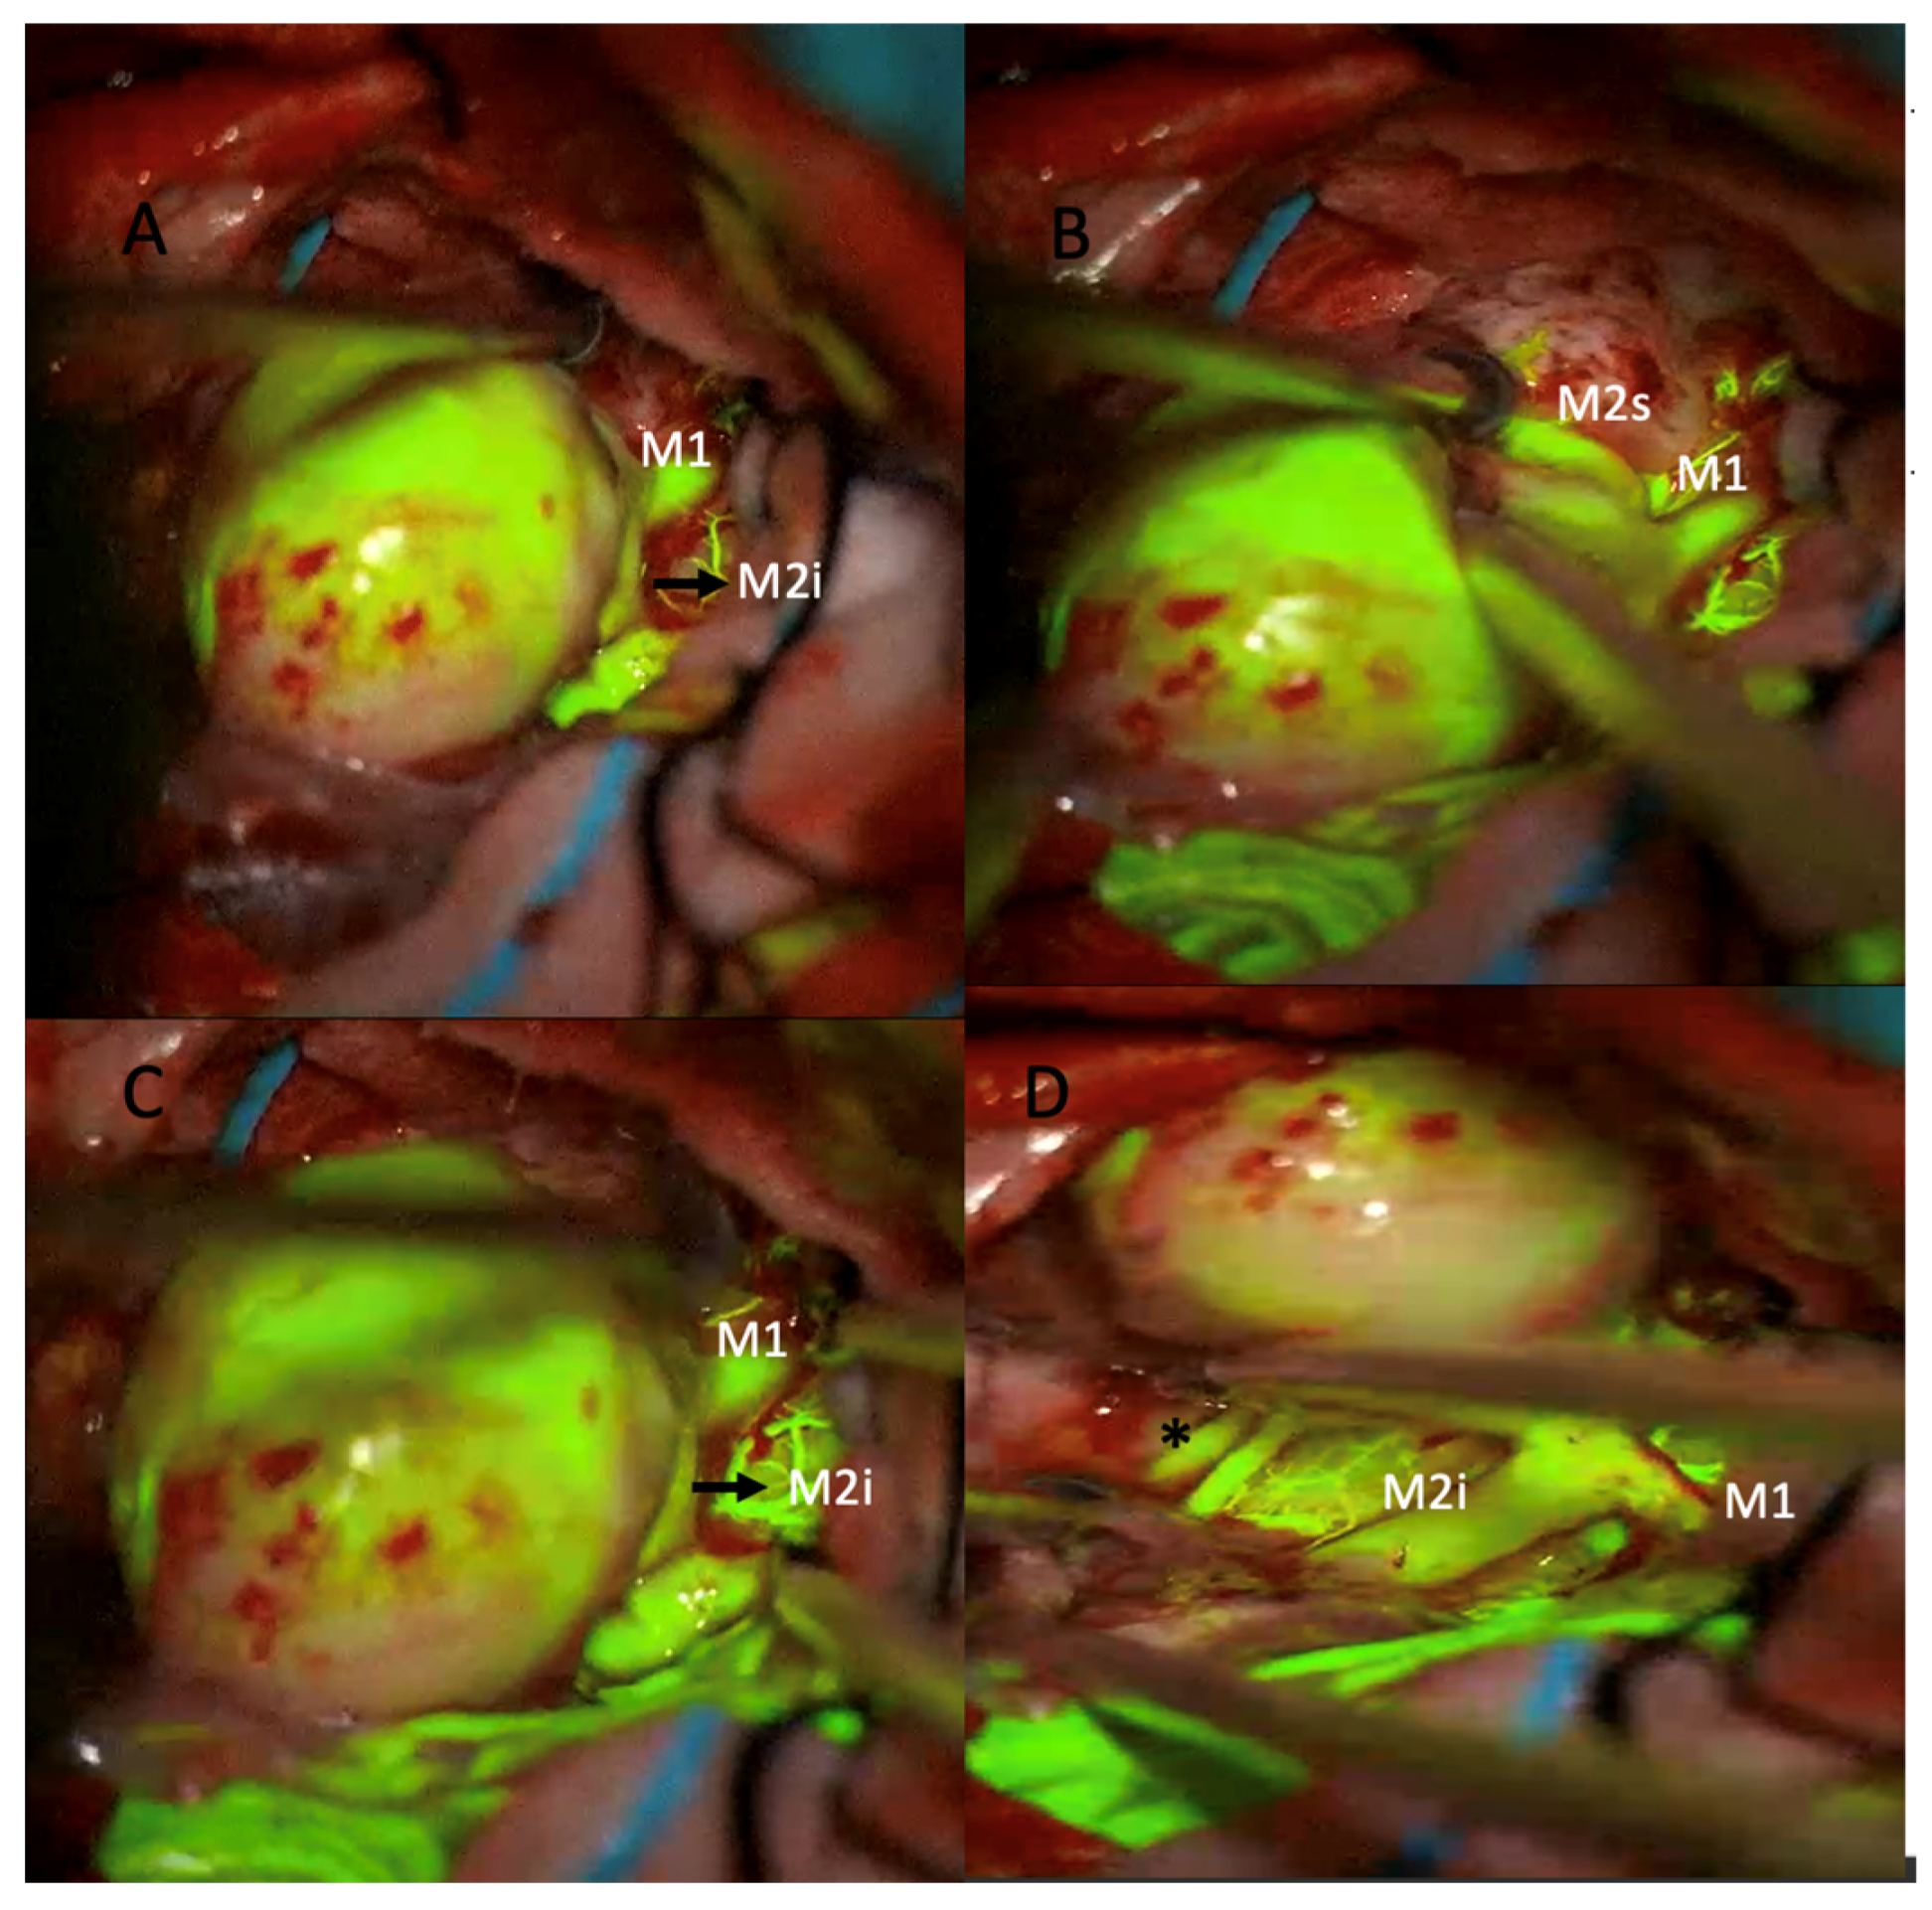

A 43-year-old male patient with no known comorbidities and an intact neurological examination was incidentally found to have a calcified giant bifurcation aneurysm of the left MCA (Figure 1).

The patient underwent surgery using the picket-fence clipping technique, during which seven Sugita fenestrated clips were applied. Intraoperative sodium fluorescein and ICG videoangiography confirmed complete aneurysm occlusion and preservation of the parent arteries (Figure 2 and Figure 3).

No abnormalities were observed in the patient’s postoperative neurological examination, and postoperative neuroradiological images showed no residual filling of the aneurysm.

Figure 2. Intraoperative microscopic views of a giant middle cerebral artery (MCA) aneurysm during microsurgical clipping using sodium fluorescein videoangiography under a yellow 560 nm filter. (A) The large aneurysmal sac is seen adjacent to the M1 segment and the inferior division of the M2 segment (M2i). (B) After further dissection, the superior division of the M2 segment (M2s) is identified. Fluorescein fluorescence highlights the patent parent and branch vessels. (C) Confirmation of perfusion in the M1 and M2i segments is achieved prior to clip application. (D) Post-clipping image showing preserved fluorescence in the M1 and M2i segments, indicating intact flow (* asterisk marks the patent M2 inferior trunk branches).